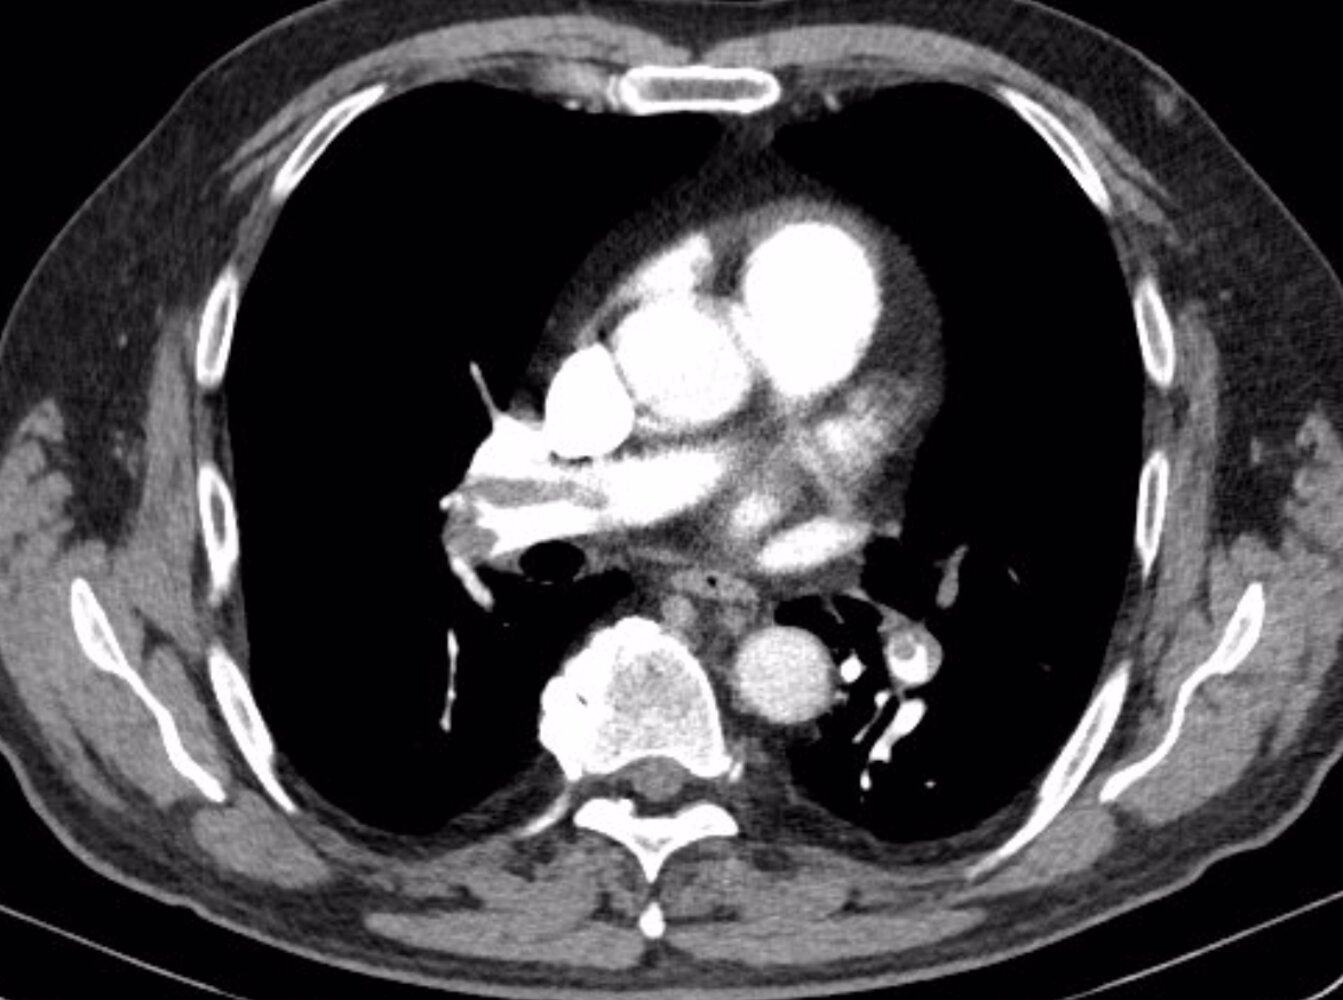

• CT pulmonary angiography: if there is a concern for pulmonary embolism (PE) [8]

• Pulmonary: PE, pulmonary hemorrhage, cor pulmonale